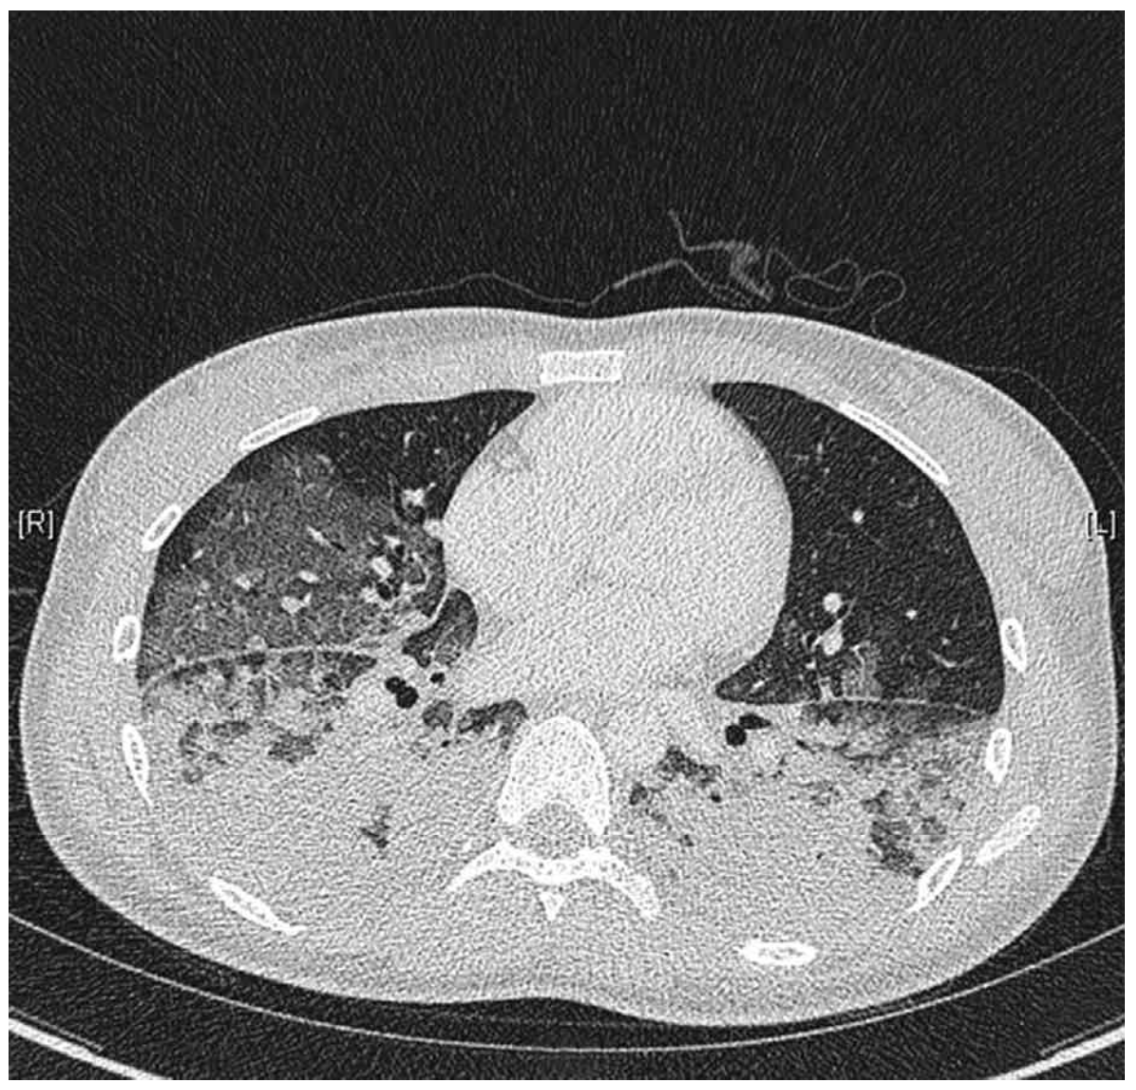

46세 여자가 2일 전부터 숨이 찬다며 병원에 왔다. 5일 전 콧물이 나고 근육통과 열감이 있었다. 3일 전부터 가래 섞인 기침을 하고 점점 심해졌다고 한다. 비흡연자이다. 혈압 80/50 mmHg, 맥박 116회/분, 호흡 36회/분, 체온 38.2°C 이다. 진찰 중에 자꾸 자려고 한다. 양쪽 가슴에서 거품소리가 들린다. 가슴 X선사진과 가슴 컴퓨터단층촬영 사진이다. 검사 결과는 다음과 같다. 처치는?

CT: Diffuse bilateral opacities and GGOs

• 더불어 1주일 이내 호흡증상이 시작되었고, CXR 및 chest CT 등 영상 소견에서 bilateral diffuse opacity를 관찰할 수 있으며, BNP가 참고치 이내로 심부전 및 체액 과부하의 증거가 없고 PaO2/FiO2 = 52/0.5~0.6 ≤ 300mmHg으로 hypoxemia가 확인된다. 따라서 해당 증례는 Berlin definition의 네 가지 기준을 모두 만족하므로 급성호흡곤란증후군으로 진단할 수 있다.